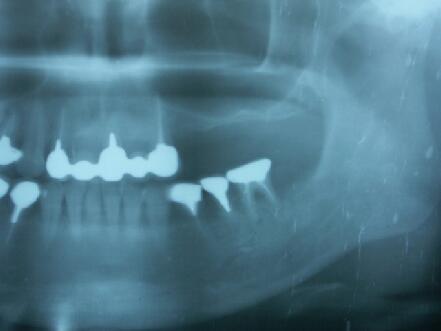

4ヵ月後のエックス線写真

4ヶ月して、当初1~3ミリしか存在しなっかた骨が7~12ミリ程度(部位によって違う)になる

4ヵ月後に最終かぶせ物をしてメンテナンスへ

予定通り4ヶ月で最終かぶせ物(メタルボンドポーセレン)を装着

この症例も十分咬合に耐える、しっかりした骨が形成されています